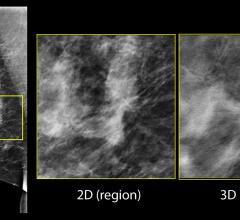

AI is also helping simplify complex tasks and help reduce the reading time on involved exams. One example of this is in 3-D breast tomosythesis with hundreds of images, which is rapidly replacing 2-D mammography, which only produces 4 images. Another example is automated image reconstruction algorithms to significantly reduce manual work. AI also is now being integrated directly into several vendors' imaging systems to speed workflow and improve image quality.